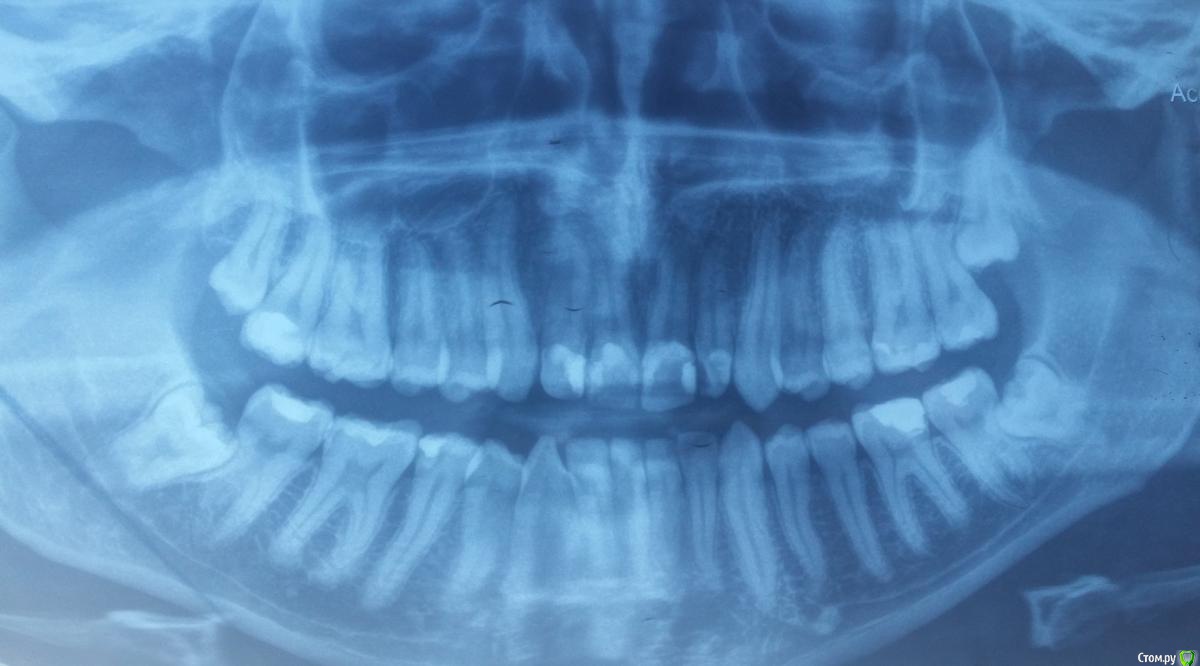

Temo2016 Опубликовано 23 апреля, 2016 Поделиться Опубликовано 23 апреля, 2016 Всем доброго дня/вечера в первую очередьМне 28 лет,зовут Тима.Последние годы у меня появились проблемы с ушами (звон,чуство залипания в ухе,чуство заглушености и.т.д) Все лор врачи распустили руки,также изза этой причины ездил в европу,результат тотже,аудиометрии и тимпонометрии на лучшем уровне,травм нету,мол с ушами всё в порядке. И вот несколько дней назад очередной лор врач посоветовал сходить к зубному (челюсть) хирургу взглянуть на зубы,тот посмотрел,сказал что есть воспаление челюстного сустава и попросил снять рентген челюсти,фото которой прилагаю внизу.Увидев рентген,сказал что надо поэтапно,операциями удалять 3 из 4х зубов мудрости,которые вызывают пока только воспаление челюстного сустава,который взаимодействует с ушамии и добавил что со временем если не удалять,будет хуже. Пробежался у других докторов,сказали тоже самое,решил спросить тут у докторов мнение.Стоит ли удалять? Могут ли они плохо действовать на уши?Спасибо всем заранее Ссылка на комментарий

Doctor Vlad Опубликовано 24 апреля, 2016 Поделиться Опубликовано 24 апреля, 2016 на этом снимке сустав вообще не вошел... восьмерки лучше убрать. но на сустав они влияют опосредованно. вот прикус ваш может и влиять Ссылка на комментарий